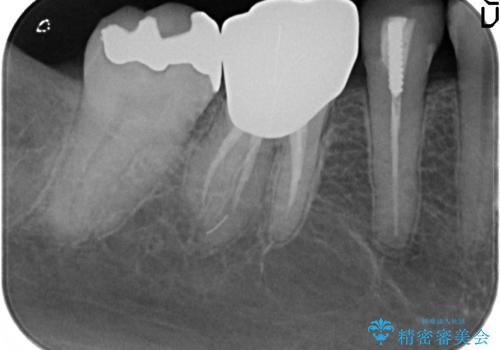

- 冷たいものを飲むと右下の奥歯が痛むので診て欲しいといらっしゃった方の症例です。

銀歯及び虫歯を除去後、より適合の良いPGA(ゴールド)インレーによる修復を行いました。